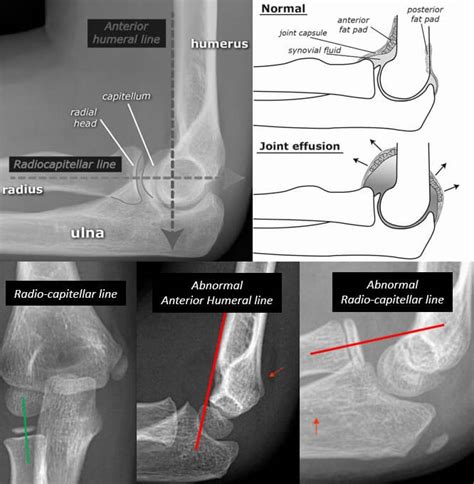

In adults, this medial prominence is completely bony, but in children, the medial epicondyle is composed of an ossification center of cartilage and bone. Fifty percent of medial epicondyle fractures are associated with an elbow dislocation.

Population has remained controversial for some time with some studies showing positive results for both operative. They are typically seen in children, and can be challenging to identify. Medial condyle fractures are intraarticular, extending into the elbow joint and require urgent open. Excision of the fractured epicondyle has been recommended for patients with comminution of the fragment as well as for fractures undergoing delayed treatment, this is probably best avoided if. Precise measurement of the degree of. The neural concerns in medial epicondylitis consist of the medial antebrachial cutaneous nerve (mabcn) and the ulnar nerve. Author response to letter to the editor. Suture fixation of a medial epicondyle fracture. Medial epicondyle fractures represent almost all epicondyle fractures and occur when there is avulsion of the medial epicondyle. Medial condyle fractures involve a fracture line that extends through and separates the medial metaphysis and epicondyle from the rest of the humerus (see image below). Featuring rami alrabaa, george popa. While the examiner palpates the patient's medial epicondyle, resisted wrist flexion and pronation. Avulsion fractures of the medial epicondyle are seen between the ages of 9 and 15, after the apophysis becomes a separate ossification nucleus from the epiphysis of the distal humerus and before it fuses with the distal humerus. Looking to download safe free latest software now. They can be classified according to the degree of displacement of the epicondyle, its association with elbow dislocation and incarceration of the epicondyle within the joint on reduction of dislocation. Because it is the site of origin of the flexor/pronator mass and the elbow lateral collateral ligaments, avulsion fractures are particularly. Primary constraints=ulnohumeral articulation(coronoid), medial collateral ligament(mcl), lateral collateral.